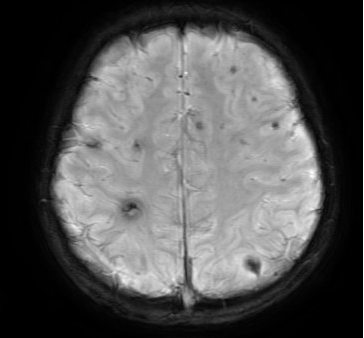

图三 洋洋术前MRI发现有多发脑梗伴出血 图四 李温斌(左一)与崔晓征(右二)为患者手术

入院时,洋洋被查出患有脑部栓塞,虽暂时还没有造成偏瘫等后遗症,但加上本身病程较长,如何将围手术期的风险降到最低成了当前最需要解决的问题。于是,由心脏外科牵头,联合血管外科、ICU、麻醉科的多位专家组成多学科讨论,对洋洋的手术方案、术中可能的风险及术后恢复等相关问题展开了探讨,最终决定此次手术先由心脏外科处理瓣膜问题,择期再由血管外科解决下肢栓塞的情况。